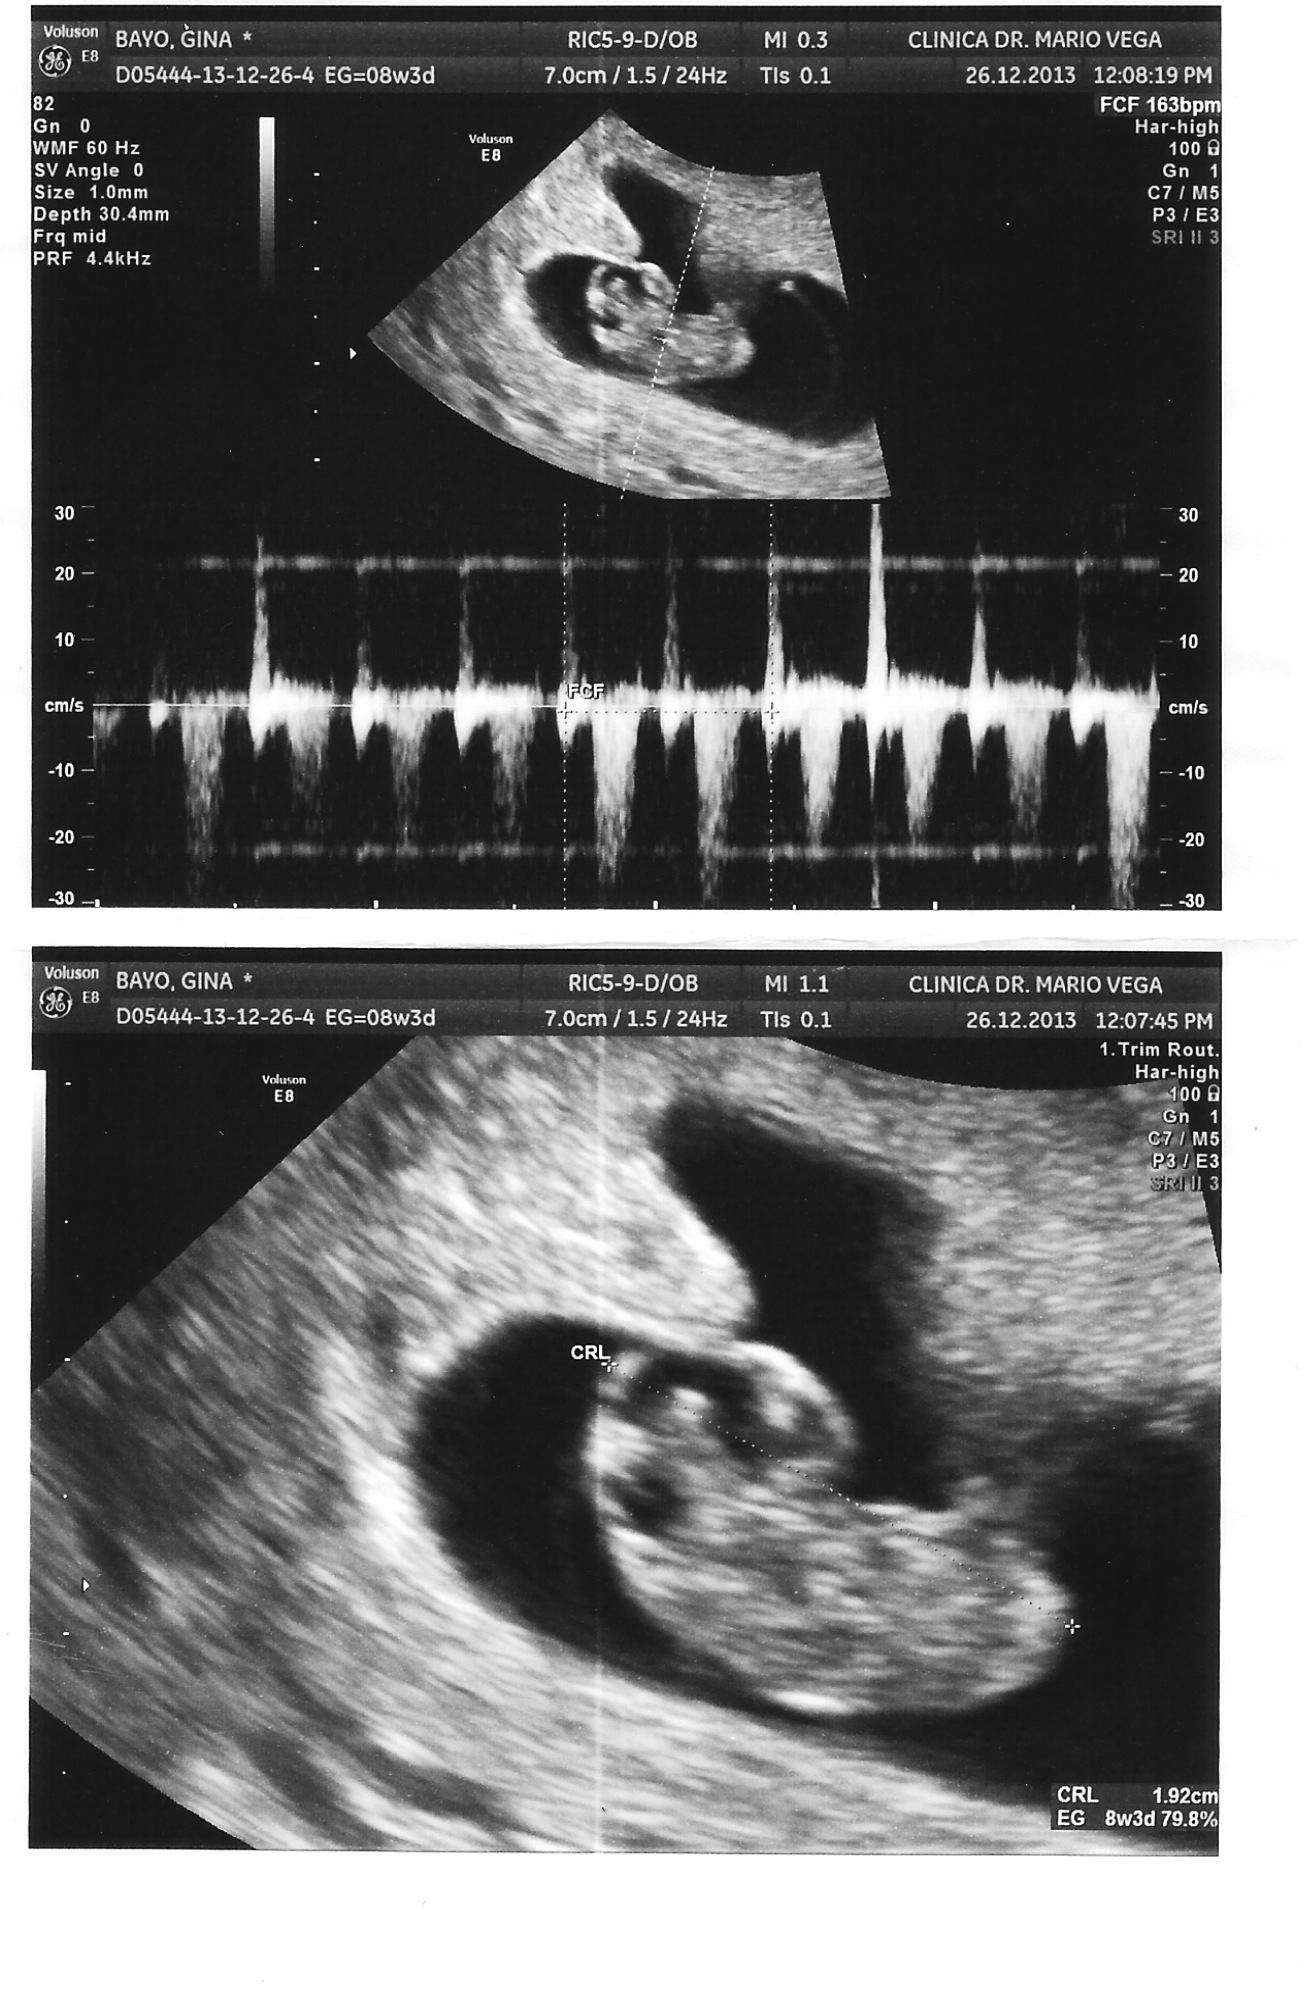

La primera cita fue a las 6 semanas y luego de una espera de 3 horas en las que ya no sabía ni cómo sentarme ni de qué hablar, me hicieron el primer ultrasonido. El doctor durante el ultrasonido puso los latidos del corazón y fue un momento emocionante, sin embargo, tenía mucho miedo porque ya había tenido años atrás, 2 pérdidas.

La siguiente cita ya nos relajamos más, gracias a Dios todo bien. Ya le avisamos al resto de la family. Todos chochos y felices.